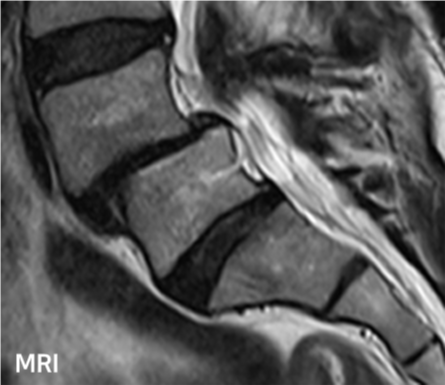

척추전방전위증 수술 전·후

2022.09.21

2022.12.30

ㆍ환자 동의를 받은 자료이며, 이미지 사진은 실물과 다를 수 있습니다.